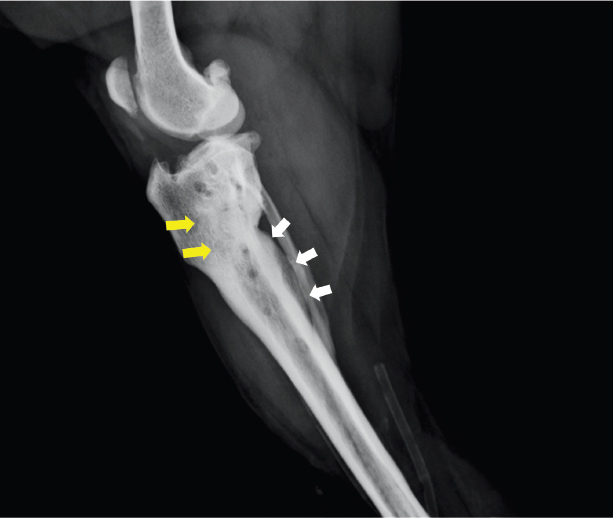

Fig. 3. Lateral view of the right hind limb on radiograph at 132 days after TPLO. An area of high radiolucency in the proximal tibia (yellow arrows) and a periosteal reaction on the caudal side of the tibia (white arrows) were observed. (TPLO): tibial plateau leveling osteotomy.

At 132 days after TPLO surgery, the purulent discharge continued, and the surgical wound was dehisced again. Blood examination again showed a marked increase in CRP level (19 mg/dl). In addition, radiography showed an area of high radiolucency in the proximal tibia and a periosteal reaction on the caudal side of the tibia, suggestive of osteomyelitis (Fig. 3). Thus, lavage of the infected site was carried out under general anesthesia. Furthermore, because of purulent discharge, a drain tube was inserted to penetrate a third screw hole from the distal side. Postoperatively, the antibiotic was changed to an intravenous administration of vancomycin (15 mg/kg) thrice daily, based on the third drug sensitivity test result. Continuous infusion of vancomycin and lavage with saline via a drain tube was carried out for 2 weeks. However, there was no remarkable improvement in the purulent discharge (Fig. 4). Hence, oral administration of rifampicin (13 mg/kg) twice daily was attempted in combination with vancomycin at 145 days after TPLO surgery. Following this, the discharge from the infected site decreased gradually and the lameness disappeared. At 154 days after TPLO surgery, the drain tube was removed. Subsequently, vancomycin was withdrawn and rifampicin was administered for another month. No noticeable side effects were observed in blood tests or physical examinations during or after administering each antibiotic. Finally, the purulent discharge disappeared and the fistula closed completely (Fig. 5). Currently, the dog has no clinical symptoms and is progressing well.